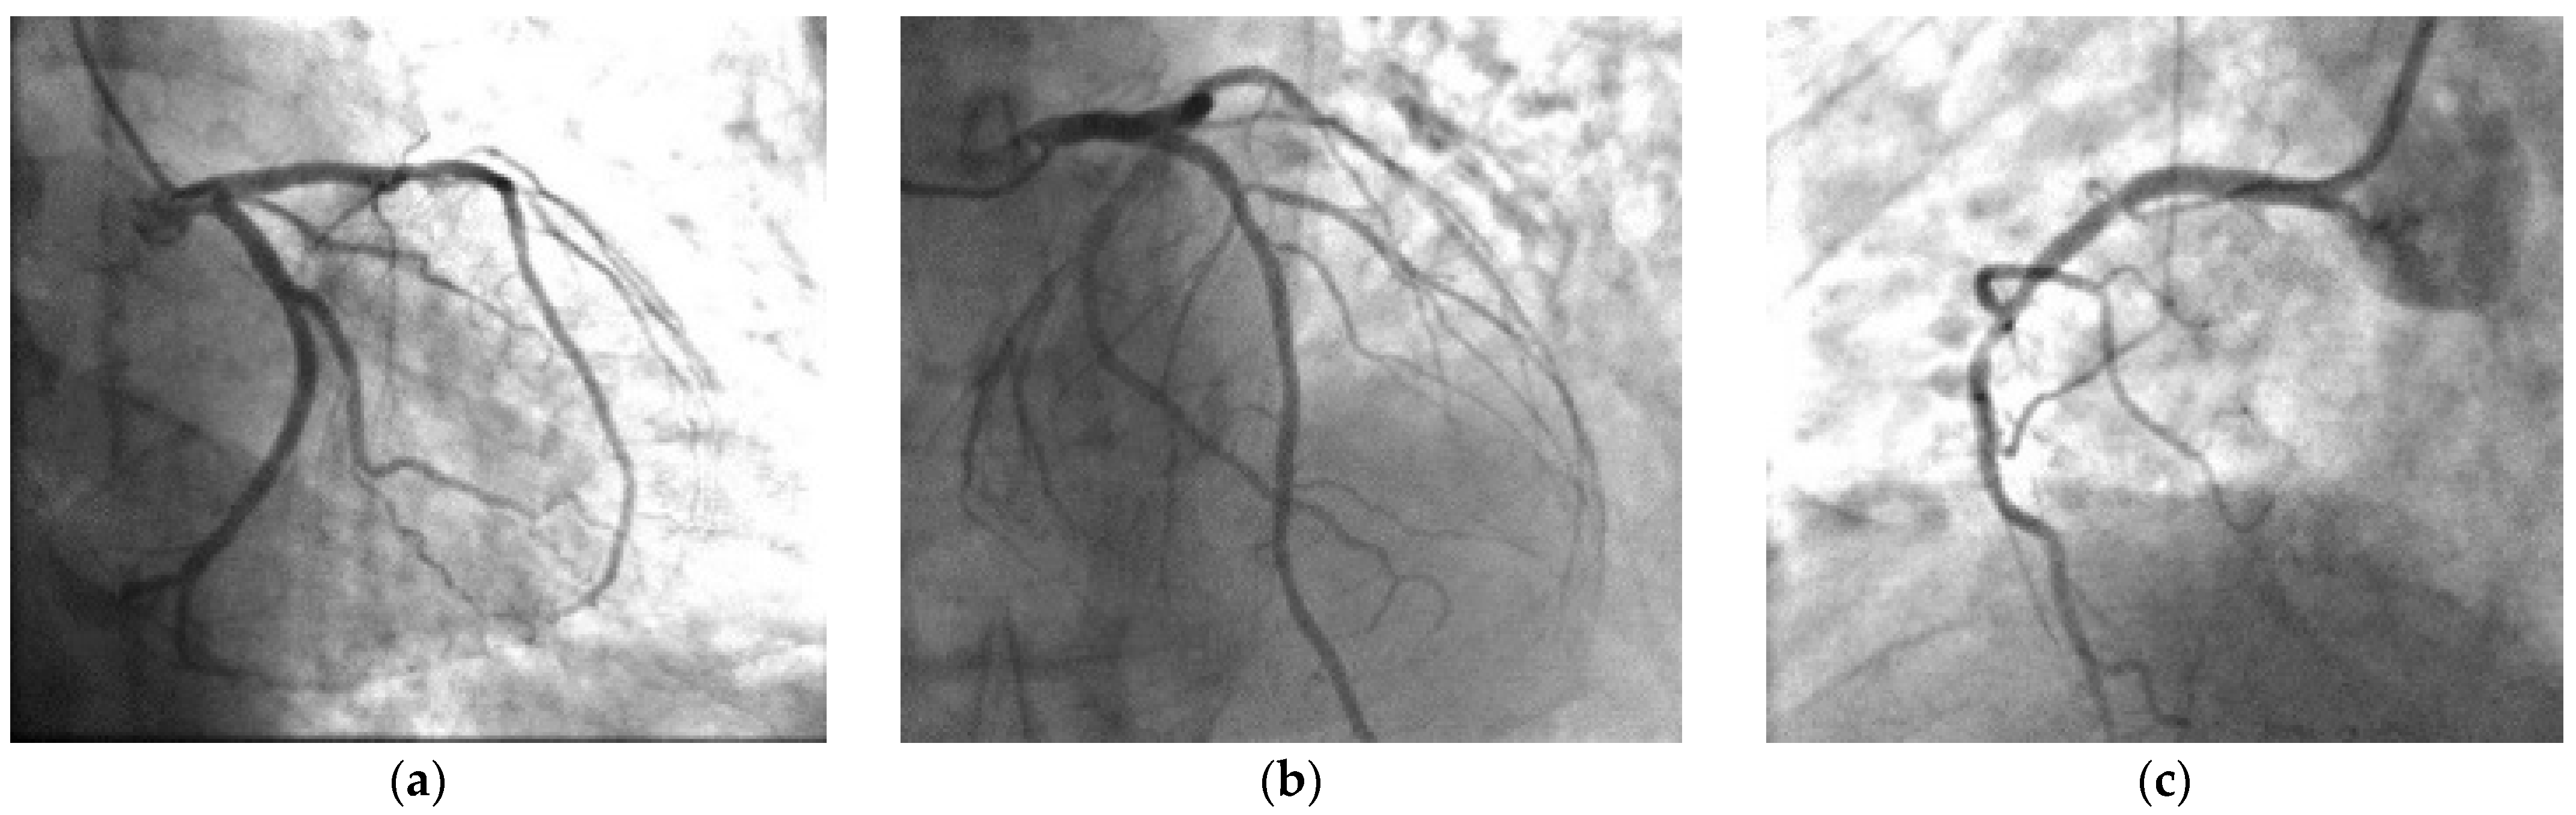

During the preparation for the procedure in the cath lab, the patient’s pain subdued. The emergency coronary angiogram did not reveal any hemodynamically significant stenosis of the coronary tree (Figure 2). There was a focal 40% stenosis of the first diagonal and a 40% focal stenosis of proximal circumflex artery, which were considered not hemodynamically significant.

Figure 2.

Cardiac catheterization. Right anterior oblique, (a) caudal and (b) cranial of left coronary anatomy (stenosis 40% on the first diagonal). Left anterior oblique, (c) cranial of right coronary anatomy (stenosis 50% on the proximal right coronary).